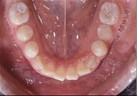

front view left buccal maxillary mandibular

Right Buccal View Frontal View Left Buccal View Maxillary View Mandibular View